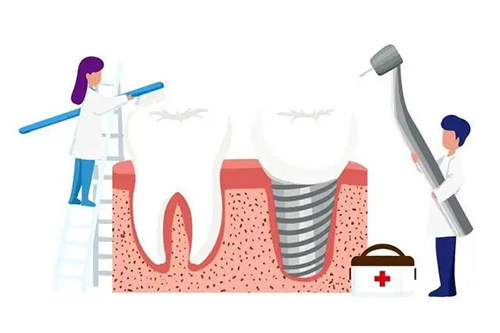

牙齿种植项目价格

单颗种植牙(基础价格):3500 - 10000 元起

多颗种植:25000 - 55000 元起

全口种植:65000 - 75000 元起